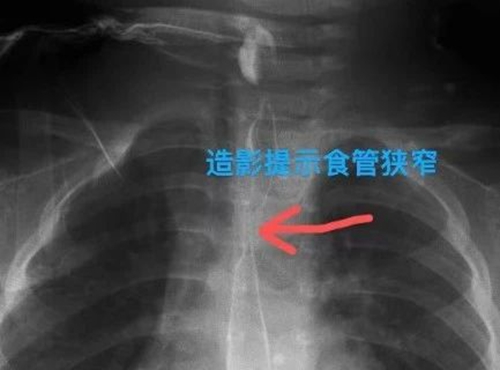

針對(duì)萌萌的病情,救治團(tuán)隊(duì)進(jìn)行對(duì)癥治療,患兒病情終于穩(wěn)定下來。但團(tuán)隊(duì)成員絲毫不敢大意,叮囑萌萌父母定期復(fù)查,及時(shí)評(píng)估食管恢復(fù)情況,并做好食管狹窄的治療預(yù)案。1個(gè)月后,萌萌復(fù)查結(jié)果提示食管出現(xiàn)明顯的狹窄,狹窄段長(zhǎng)約2cm,最窄處僅有3mm。